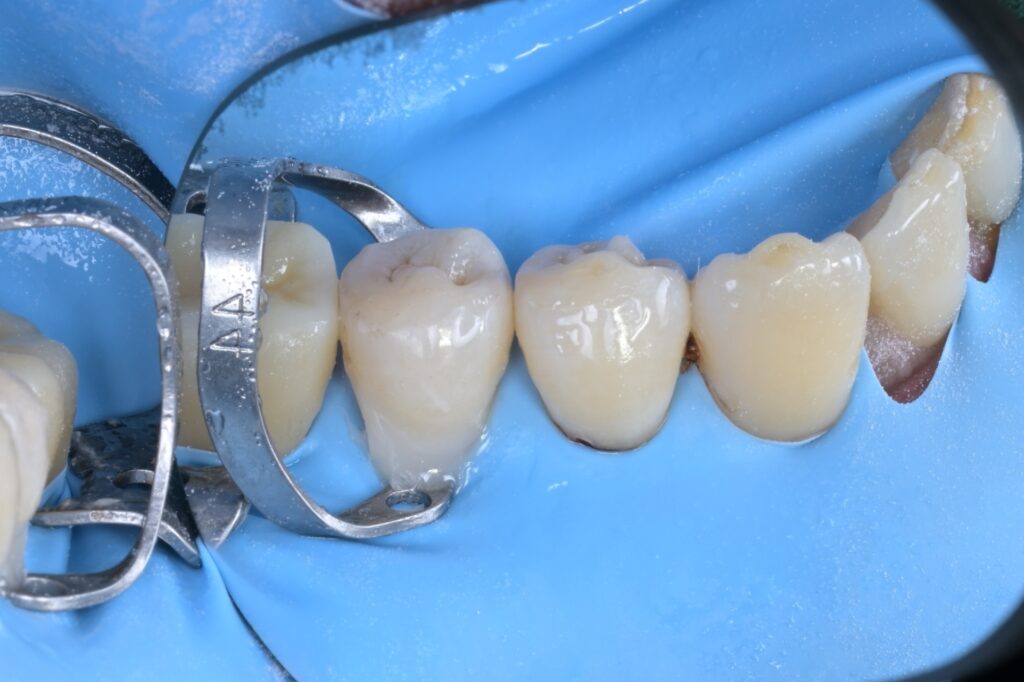

STEP 6. 정밀 레진 빌드업

확보된 시야를 바탕으로 송곳니와 작은 어금니도 꼼꼼하게 레진을 쌓아 올립니다. 치아 사이사이의 미세한 틈까지 놓치지 않고 원래 모양대로 복원합니다.